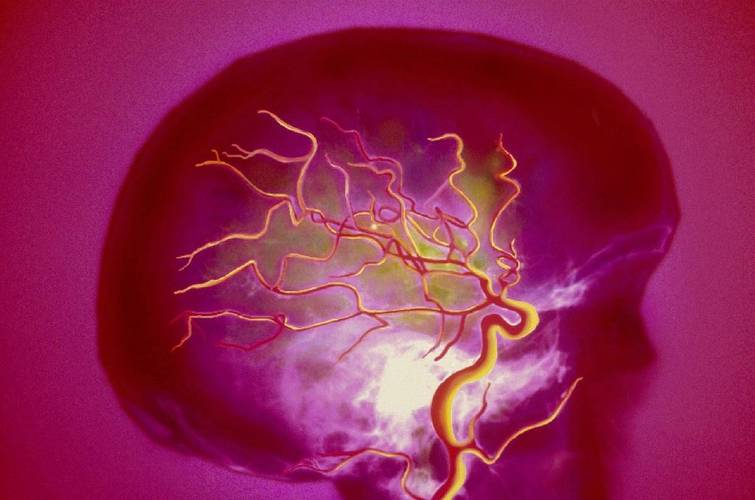

脑梗病人眼球发红可能的原因分析

我们可以将原因分为两大类:与脑梗直接或间接相关的原因,以及与脑梗无关但需要警惕的常见原因。

与脑梗直接或间接相关的原因(最需要警惕)

这类情况通常比较严重,预示着病情有变化或出现了新的问题。